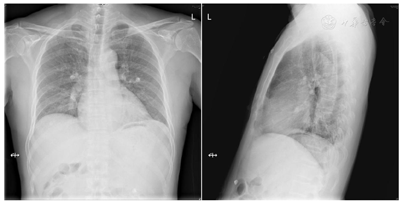

2019年10月8日胸片(远达+左侧):两肺纹理大致正常,未见实变;主动脉结偏宽;肺动脉段平直;左室圆隆;心胸比:0.51(图12)。